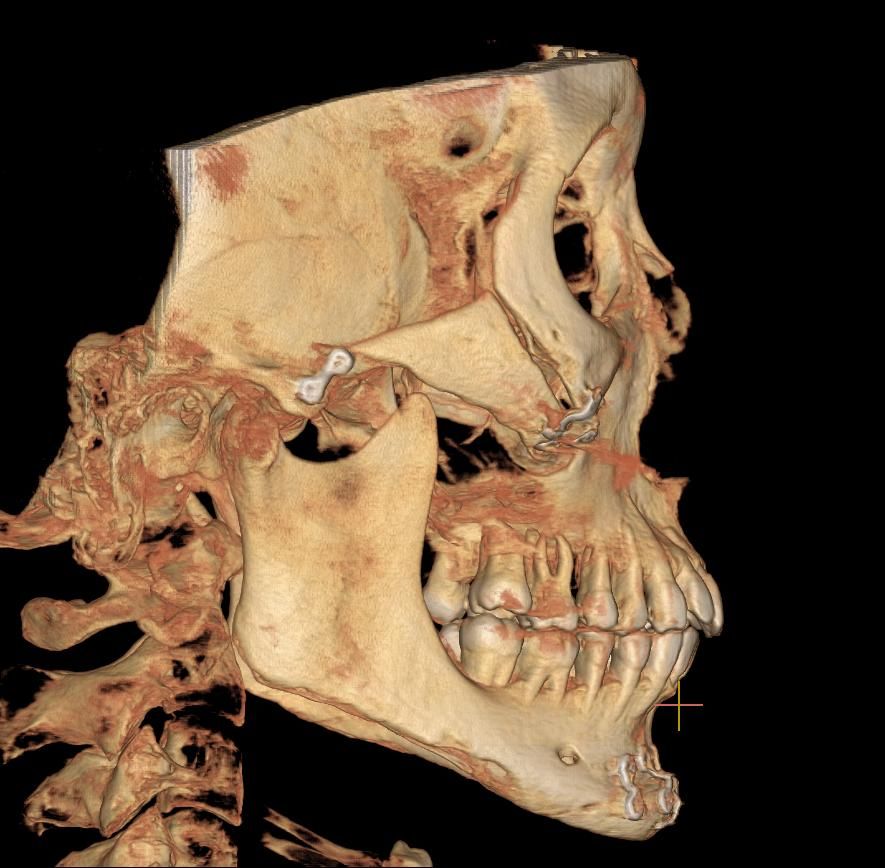

저 광대뼈 불유합이죠?ㅋㅋㅋㅋㅋㅋ

아니 제가 광대뼈 축소술 한지 이제 86일차인데 뼈가 아직도 안붙었어요 ㅋㅋ통증도 아직도 있고 근데 병원에서는 계속 뼈가 잘 붙는중이래요 ㅋㅋㅋㅋㅋㅋㅋ아니 의사님들 지금 제가 뼈가 잘붙고 있는걸로 보이나요??ㅋㅋㅋㅋ일상생활도 지금 못하고 있고 하 ㅋㅋㅋㅋ86일째인데 아직도 저렇게 조금 벌어져있는거 정상이에요? 성형외과 못믿으니까 정형외과 의사분들께 여쭤봅니다 하 ㅋㅋㅋ개월 수 말고 도대체 몇일째까지 기다려야 하는거에요?? 불유합 판정되려면?ㅋㅋㅋㅋㅋㅋㅋㅋㅋ아니 너무 화나네..진짜 솔직하게 말해줘요. 너무 늦으면 안되니까 그냥 불유합인 것 같으면 바로 병원가서 그냥 티타늄 박고 재수술하고 일상생활하게...ㅋㅋ

• 1번 째 사진